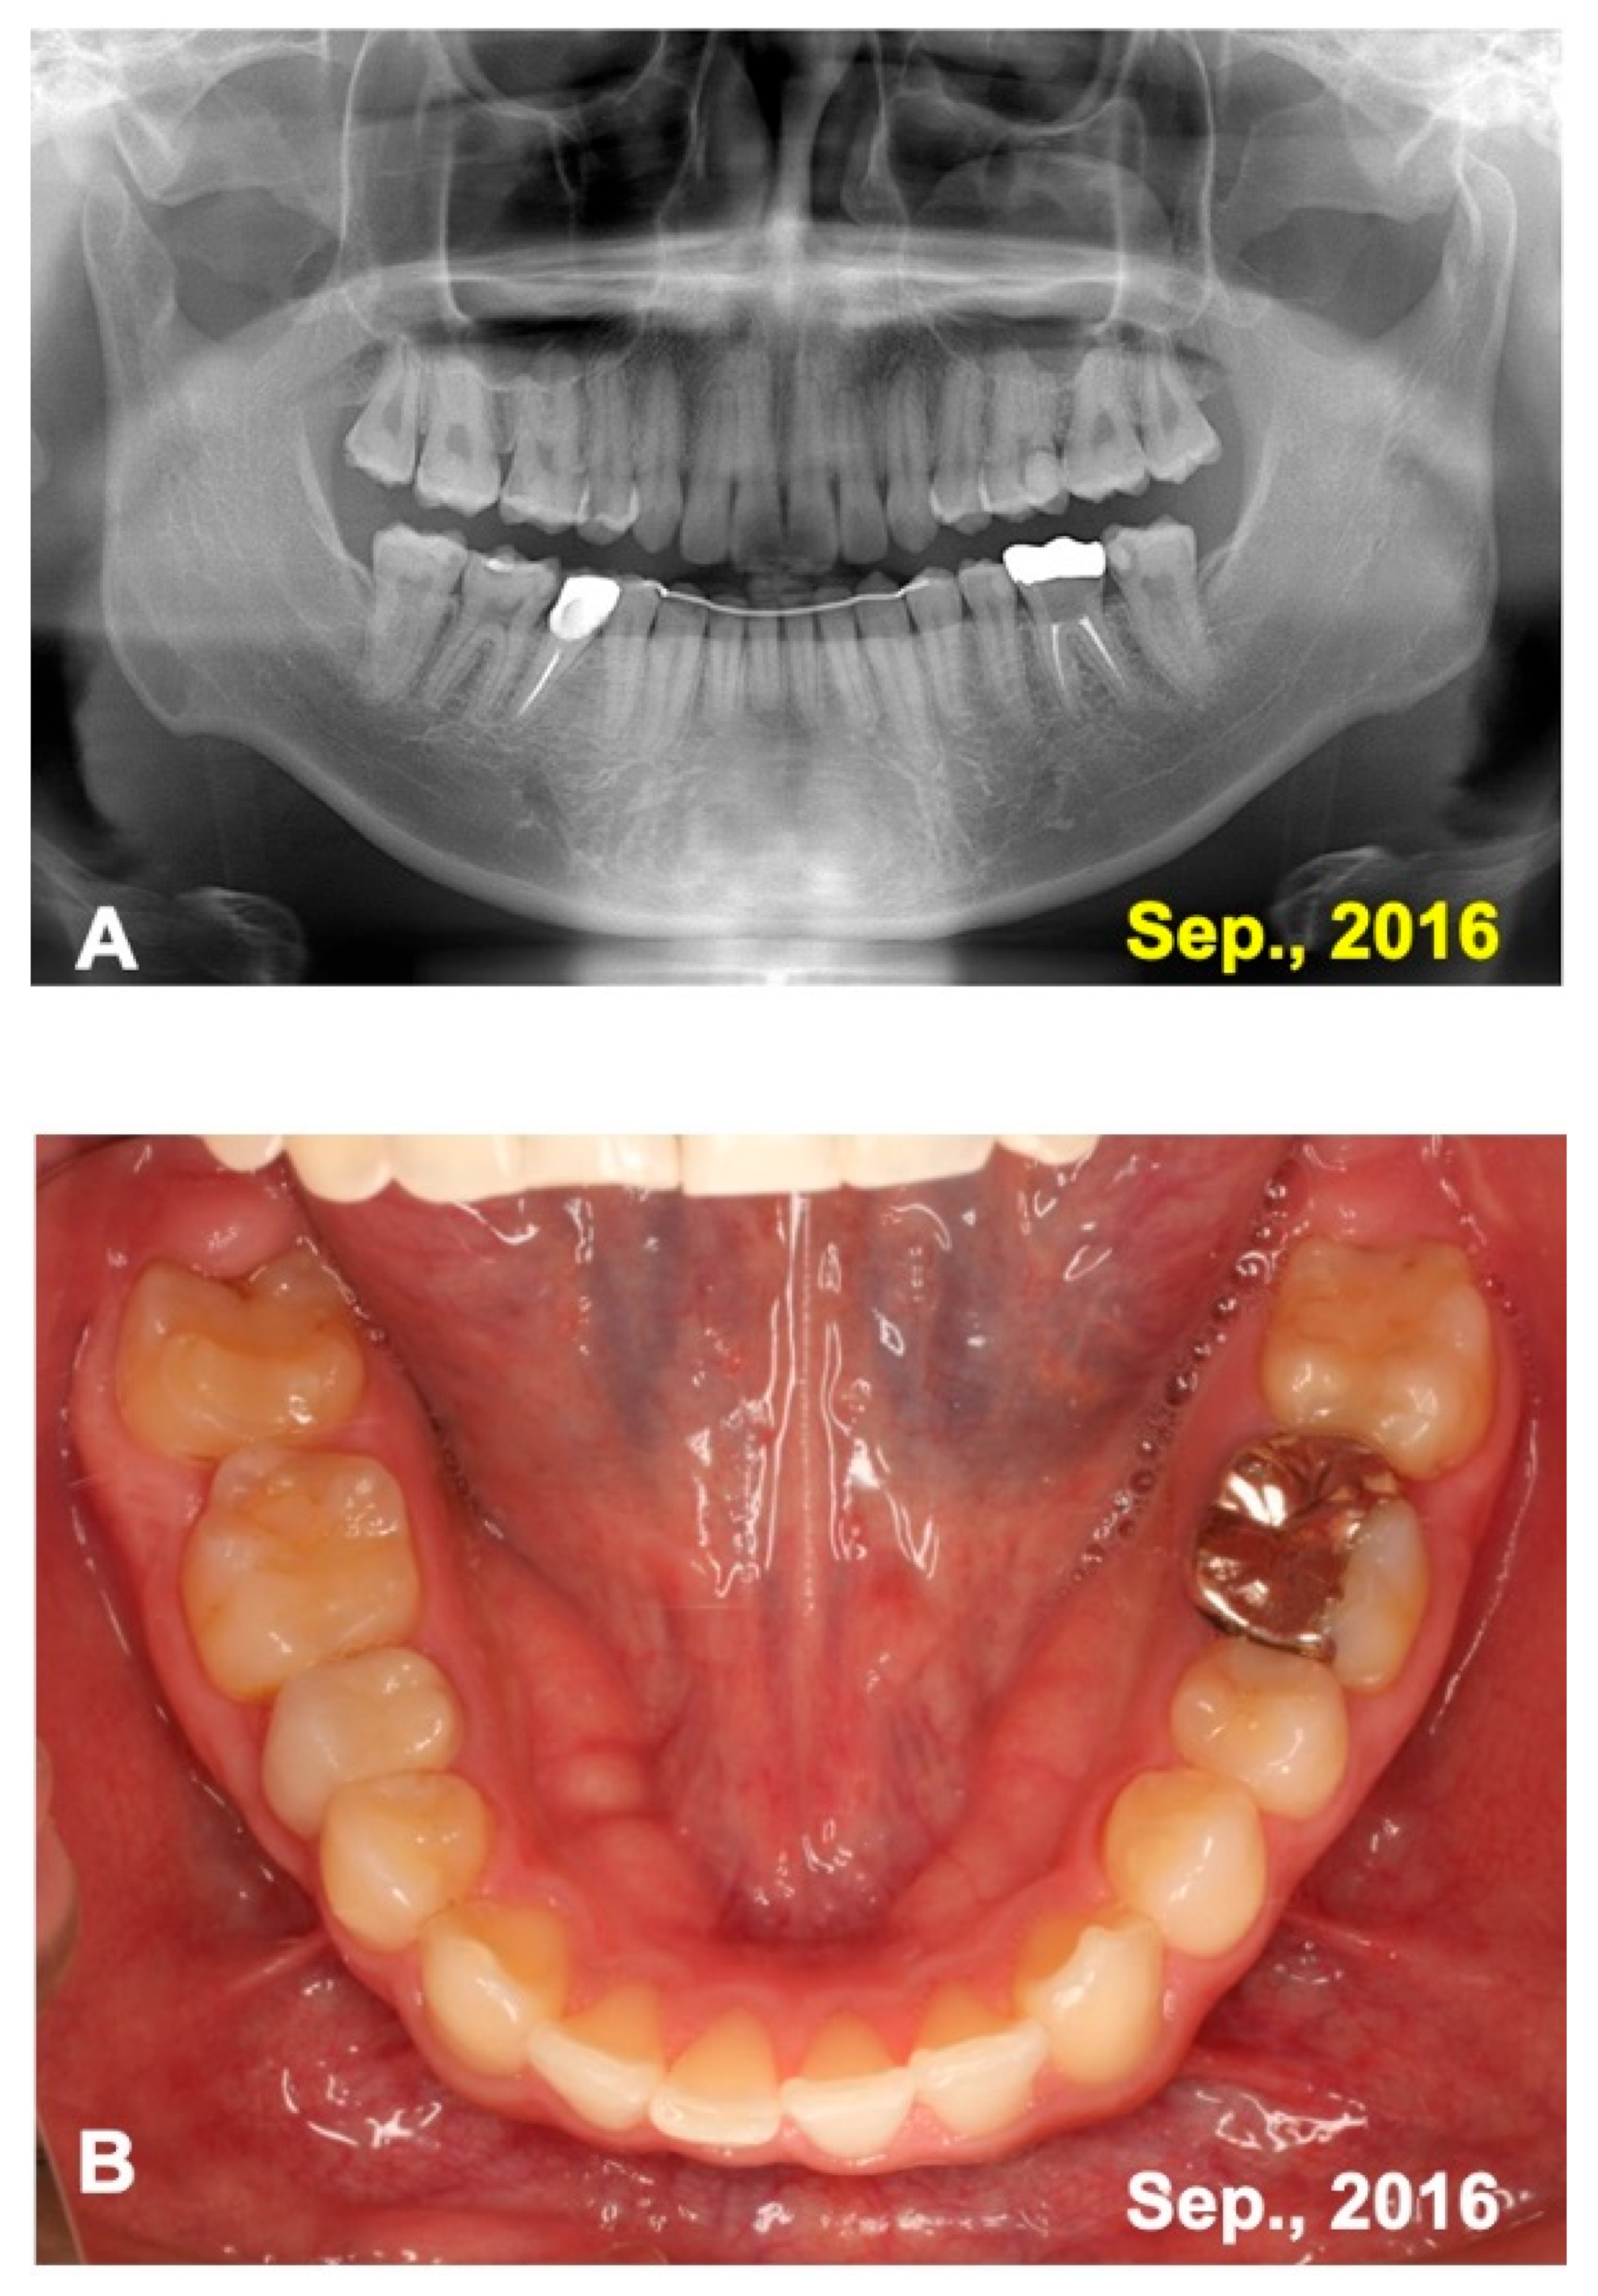

A 16 year-old-male was introduced from a private orthodontic dental clinic to our dental unit in 2011. The patient presented with a congenital missing lower left second premolar (#45), examined on initial panoramic X-ray photo (Figure 1). He had lost a milk tooth (#4E) a few weeks previously. Clinical diagnosis revealed a congenital missing tooth (#45), crowding, and maxillary protrusion. His medical history was unremarkable.

Figure 1.

Initial views of panoramic X-ray photo and oral before orthodontic treatment. Arrows indicating #14 for transplant and #24 for pDDM. Arrowhead showing congenital missing tooth (#45).